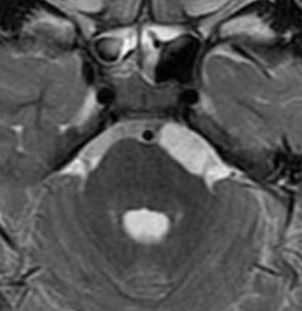

МРТ головного мозга. Т2-взвешенная аксиальная МРТ. Эпендимальная киста.

Эпендимальные кисты встречаются очень редко. Они представляют собой врождённую отшнуровку внутри желудочков или цистернах. При МРТ головного мозга контур кисты четкий, сигнал ликворной интенсивности или чуть светлее за счет отсутствия пульсации и примеси белка, структура однородная. В отличие от кист прозрачной перегородки при МРТ головного мозга видно, что она не расщеплена, а смещена.